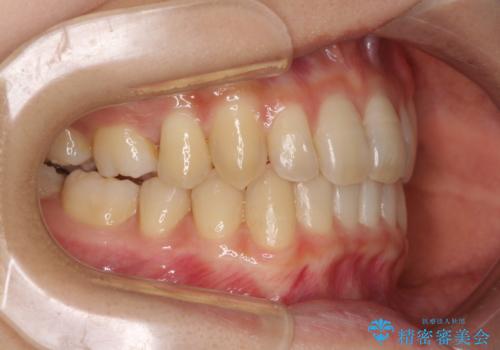

奥歯の反対咬合 上顎骨を拡大してインビザラインで矯正

- 奥歯の反対咬合を気にして来院された患者様です。

反対咬合は上顎骨の幅が下顎骨よりも小さいことが原因なので、拡大装置により骨幅を広げて上下関係を改善し、その後インビザラインにて歯並びを整えることとしました。

反対咬合が改善され、食いしばり癖もなくなり、顎関節の負担が軽減されました。

上顎骨を拡大したことで前歯に隙間ができ、1ヶ月ほど恥ずかしい時期がありましたが、しっかりとした咬み合わせに仕上がり、患者様には大変満足していただきました。